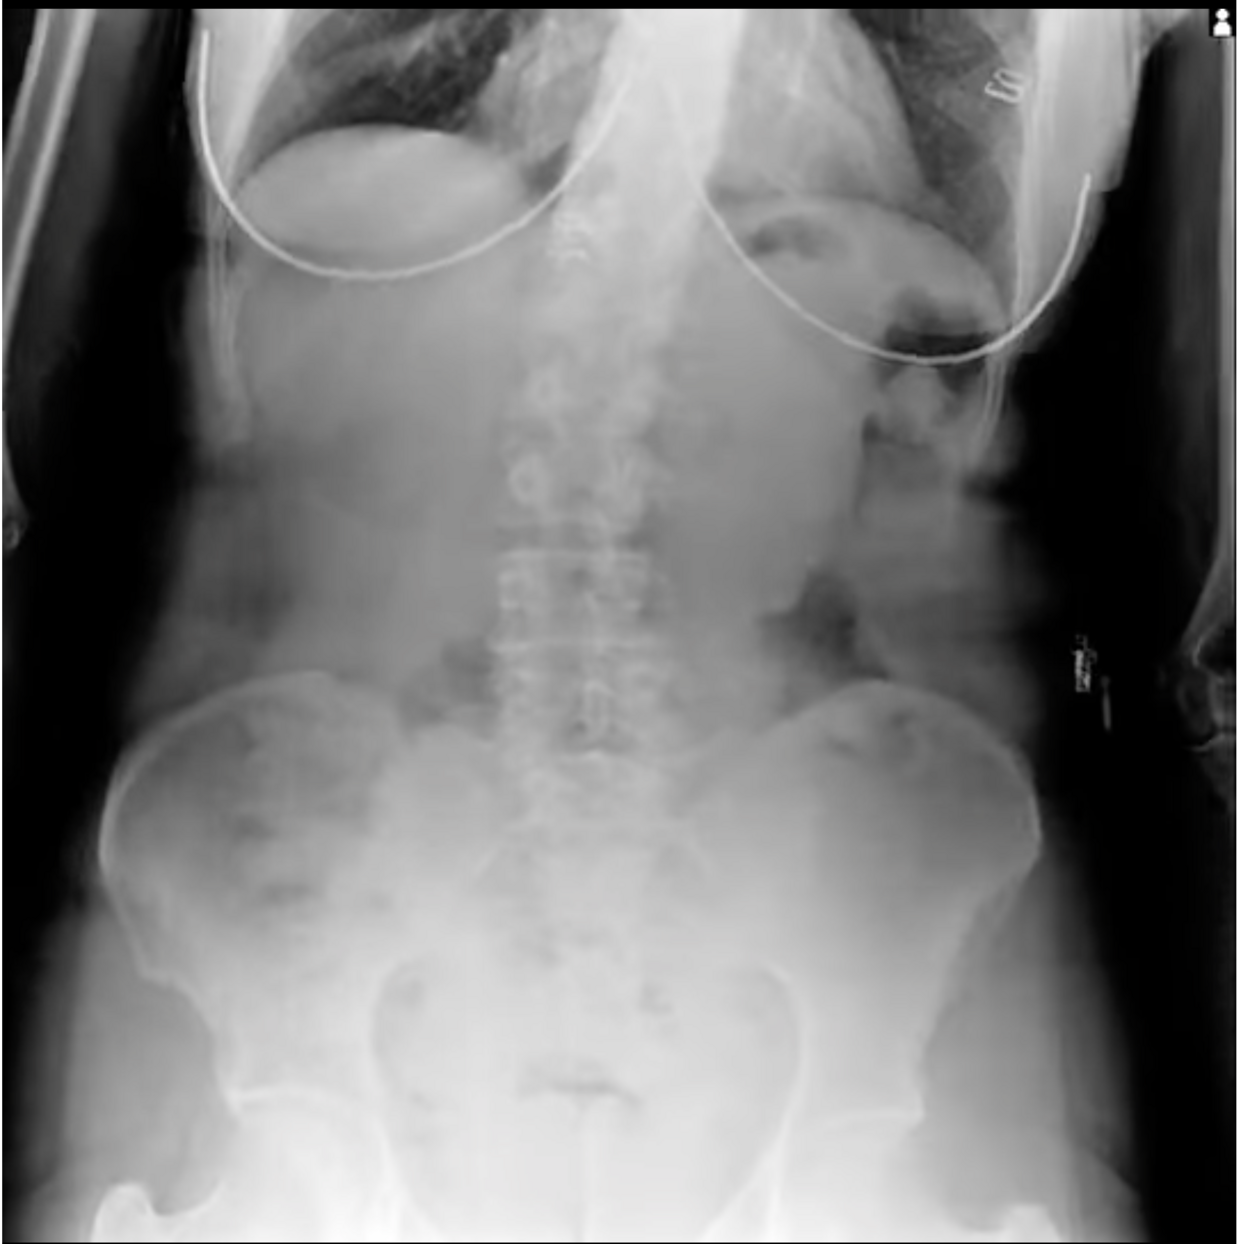

Dynamic Digital Radiography (DDR) allows you to observe movement like never before. This novel low-dose X-ray imaging technique enables visualization of anatomy in motion.

The DDR can acquire up to 15 sequential radiographs per second and play them back as a cine loop, allowing you to observe the physiological cycle and as individual radiographic images (up to 17″x 17″ in size). This advancement in digital X-ray technology is FDA-approved and available in many of our systems. DDR is X-ray that moves!